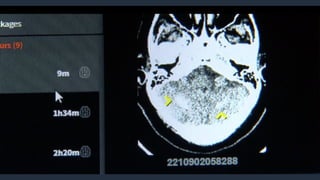

NÚCLEO DE INOVAÇÃO DO

https://radvid19.com.br/

© 2020, AmazonWeb Services, Inc. or its Affiliates. NÚCLEO DE INOVAÇÃO DO HOSPITAL DAS CLÍNICAS https://radvid19.com.br/